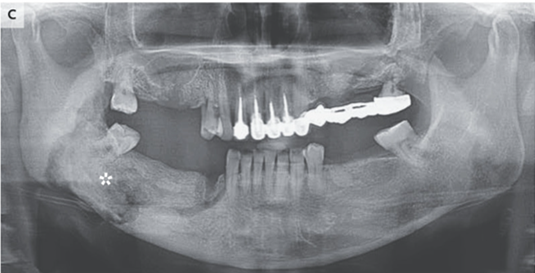

X-pでは右下顎に境界不明瞭な透過性亢進領域を認めた。

臨床上骨壊死が疑われた。